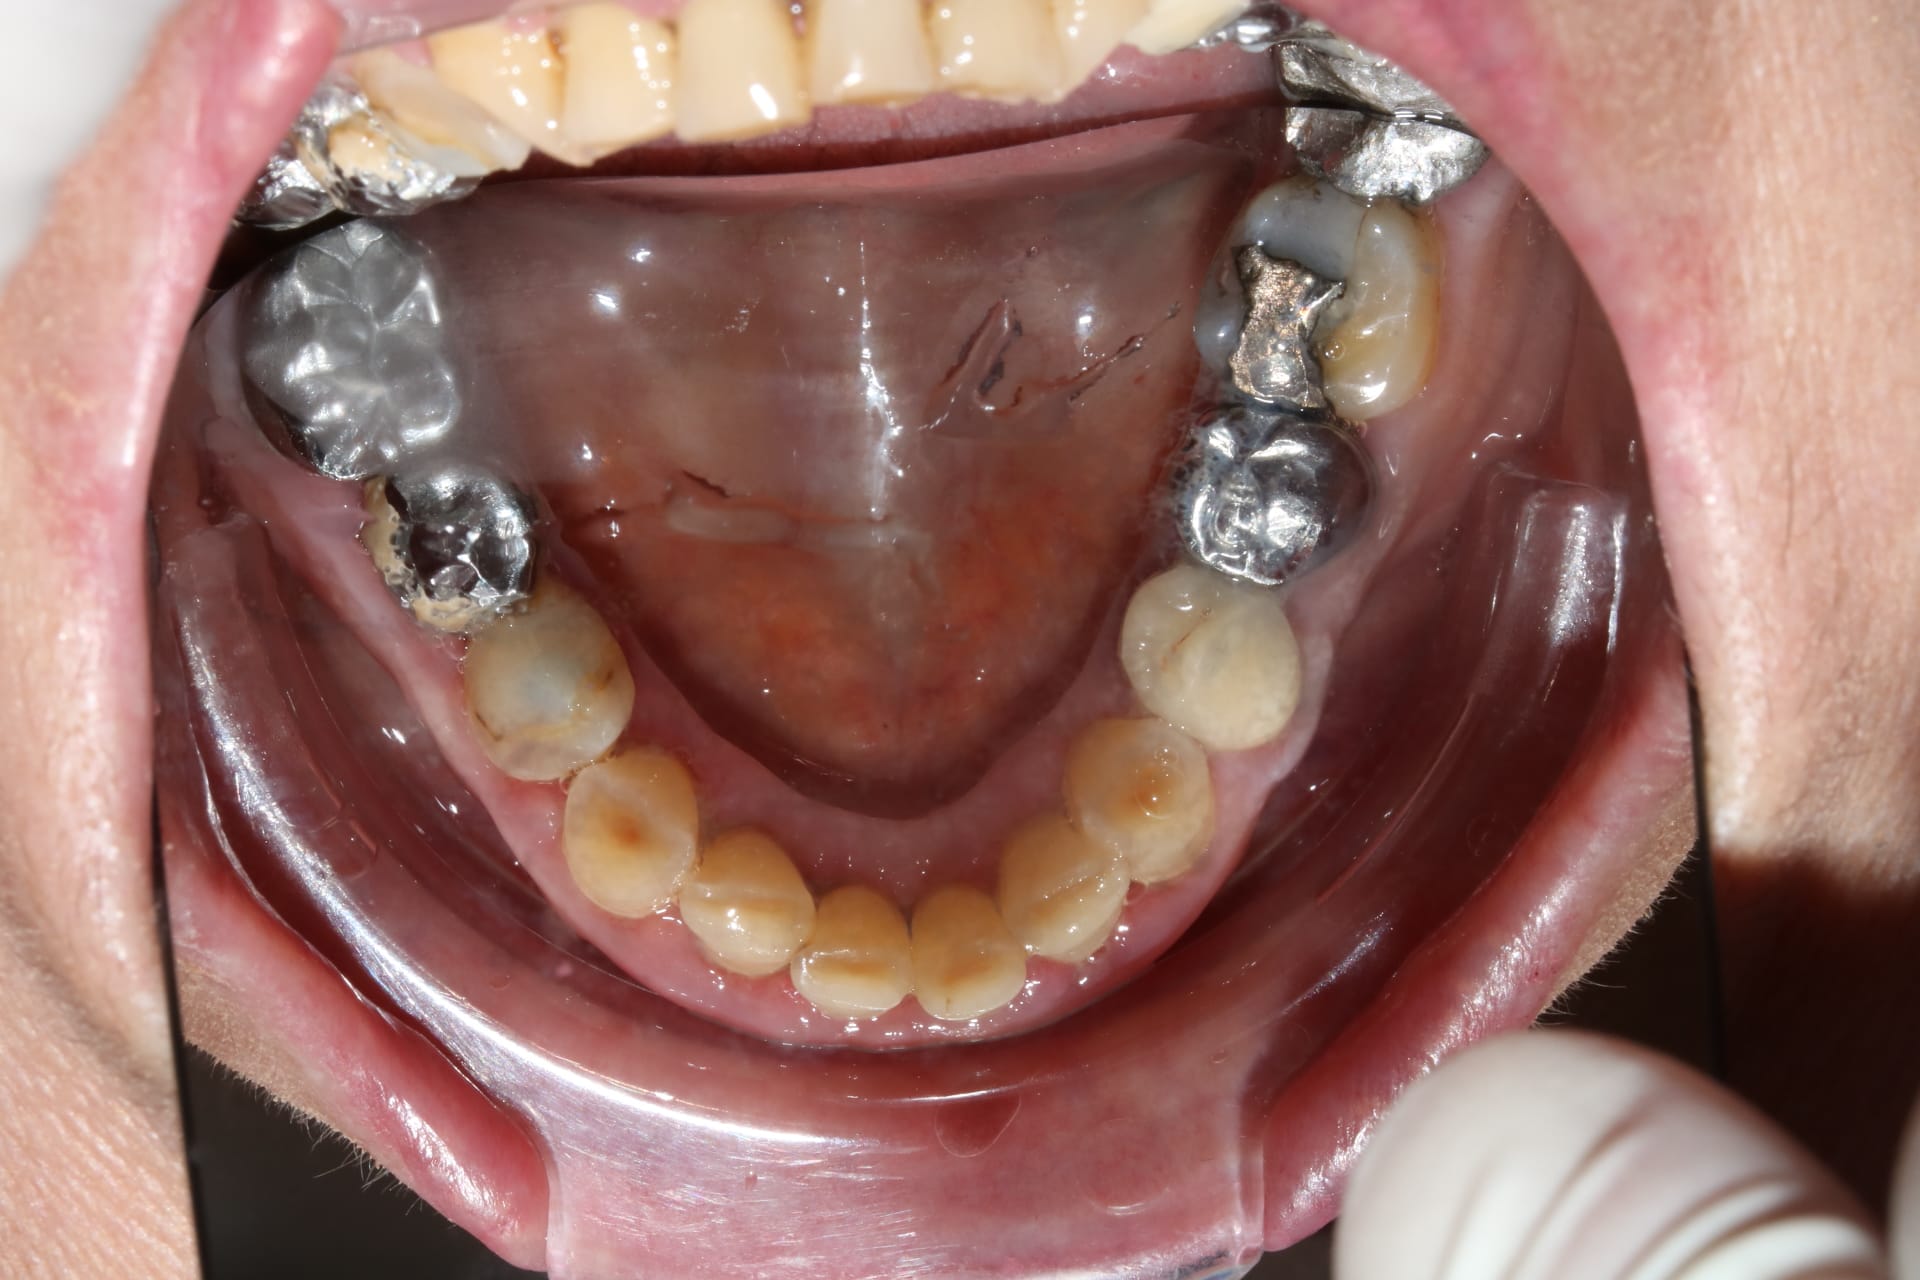

Bon , si tu ne regardes que la photo du bas :

tu as l impression que c est pas trop mal , hein?

et pourtant quand tu emboîtes le haut , ça s emboîte bien , mais tu vois bien que c est tout tordu qu il y a un truc qui ne va pas .

C est donc que le bas ne va pas non plus .donc faut couronner TOUTES les dents .

Pour le bas : à part de 33 à 43 tous le reste est sculpté de main de dentiste et prothésiste à la truelle. Donc .... j'ai pas confiance.

Il faut que mentalement tu le vois sans dents , genre complet h+b .

un complet haut et bas , tu sais faire , bien tu fais le raisonnement comme pour un complet haut et bas , sauf qu il y a des dents .